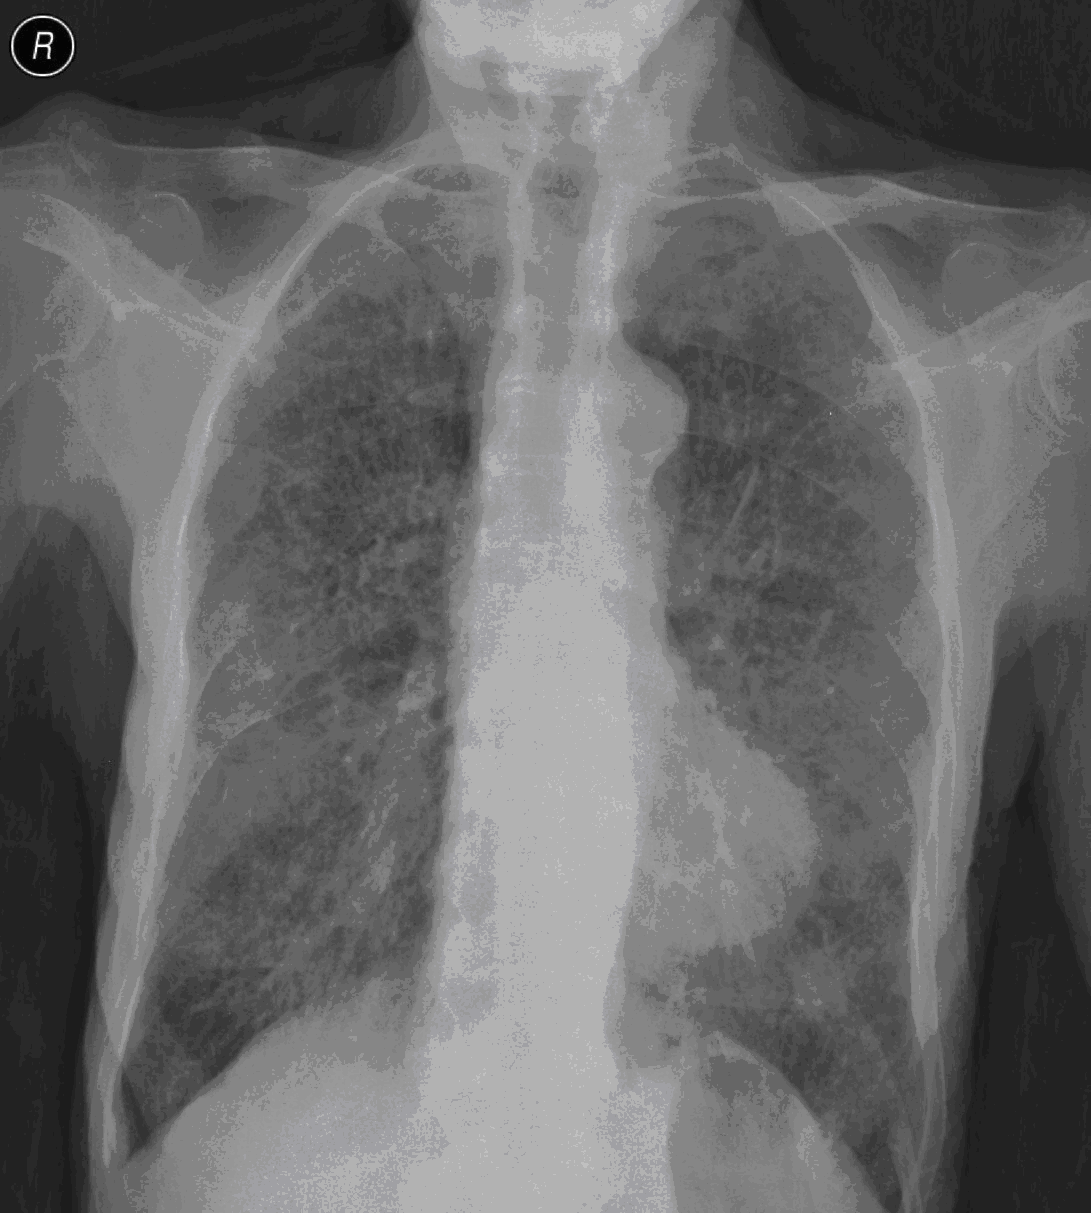

15. Atypical interstitial lobar pneumonia a.) CT b.) radiograph

45 year old man. He had a chill, serious cough, yellow-green tracheal excretion.

Left-sided lymphadenopathy next to the aortic arch on the left. Irregular infiltrations (opacities) in the lung parenchyma in subpleural and LUL dominance. (by the contribution of Zsuzsanna Monostori, MD, PhD)